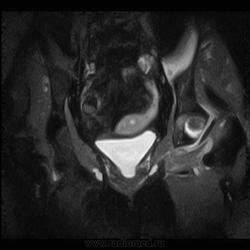

Пациентка 1944г. р. Жалобы на боль области сустава в течении месяца. Температуры не отмечала. Серьезных травм со слов не было. Внешний осмотр новых данных не дал.

А как вам стенка прямой кишки?

Да, еще подвздошная область.

Подозрительная, но неубедительно пока.Ни одного сагитталла не вижу с прямой кишкой.Нужно дообследовать однозначно.

Ну сагитталы на сустав делали..придет за ответом дообследую и кишку, хотя она вполне доступна и для ректороманоскопии.